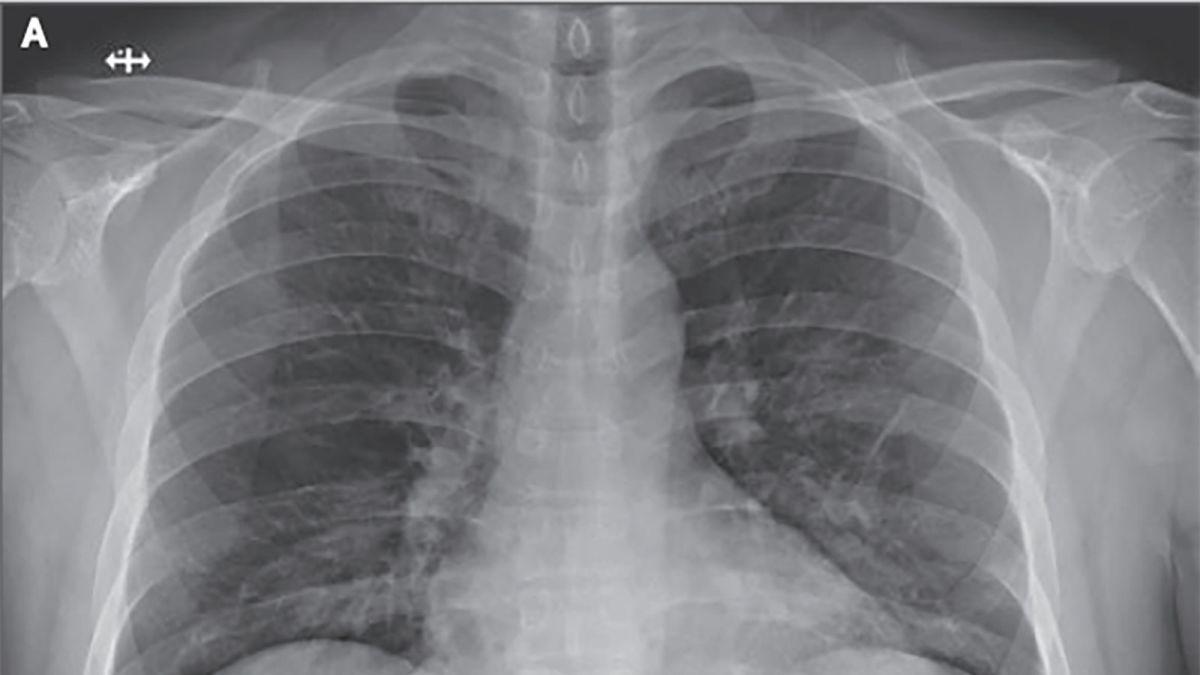

Asintomáticos de COVID-19 también sufren fuerte daño en los pulmones de forma silenciosa

Un estudio reciente realizado en distintos hospitales de Wuhan demuestra que los casos de COVID-19 que son asintomáticos también sufren daños severos en los pulmones, incluso se han casos de muertes repentinas. El estudio describe los cambios patológicos del pulmón en las tomografías de pacientes completamente asintomáticos.  Los investigadores encontraron lesiones consistentes con inflamación del tejido